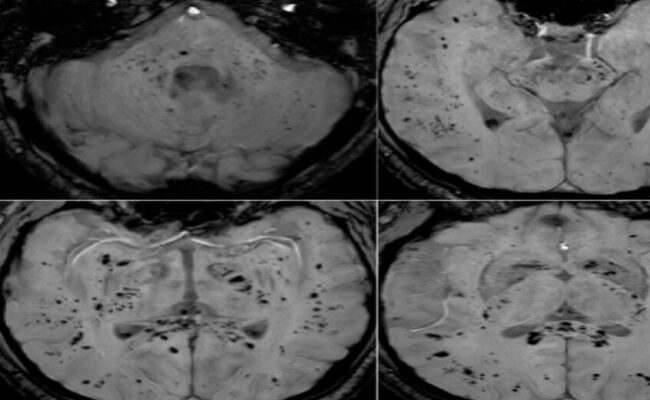

كشفت دراسة حديثة أجراها باحثون في جامعة غوتنبرغ السويدية أن عدداً كبيراً من الشباب الذين توفوا جراء الموت القلبي المفاجئ كانوا قد طلبوا رعاية طبية قبل الحادثة بفترة وجيزة، ما يشير إلى إمكانية تحديد الأشخاص المعرضين للخطر في وقت مبكر. وأوضح الباحثون أن تخطيط كهربية القلب (EKG)، وهو فحص بسيط وغير مؤلم يقيس النشاط الكهربائي…